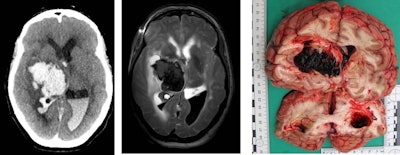

Brain hemorrhage due to hypertension or vessel anomalies is a natural death -- this finding in the postmortem imaging can allow such cases to be closed without open invasive autopsy. Images courtesy of Prof. Michael Thali.CT triage